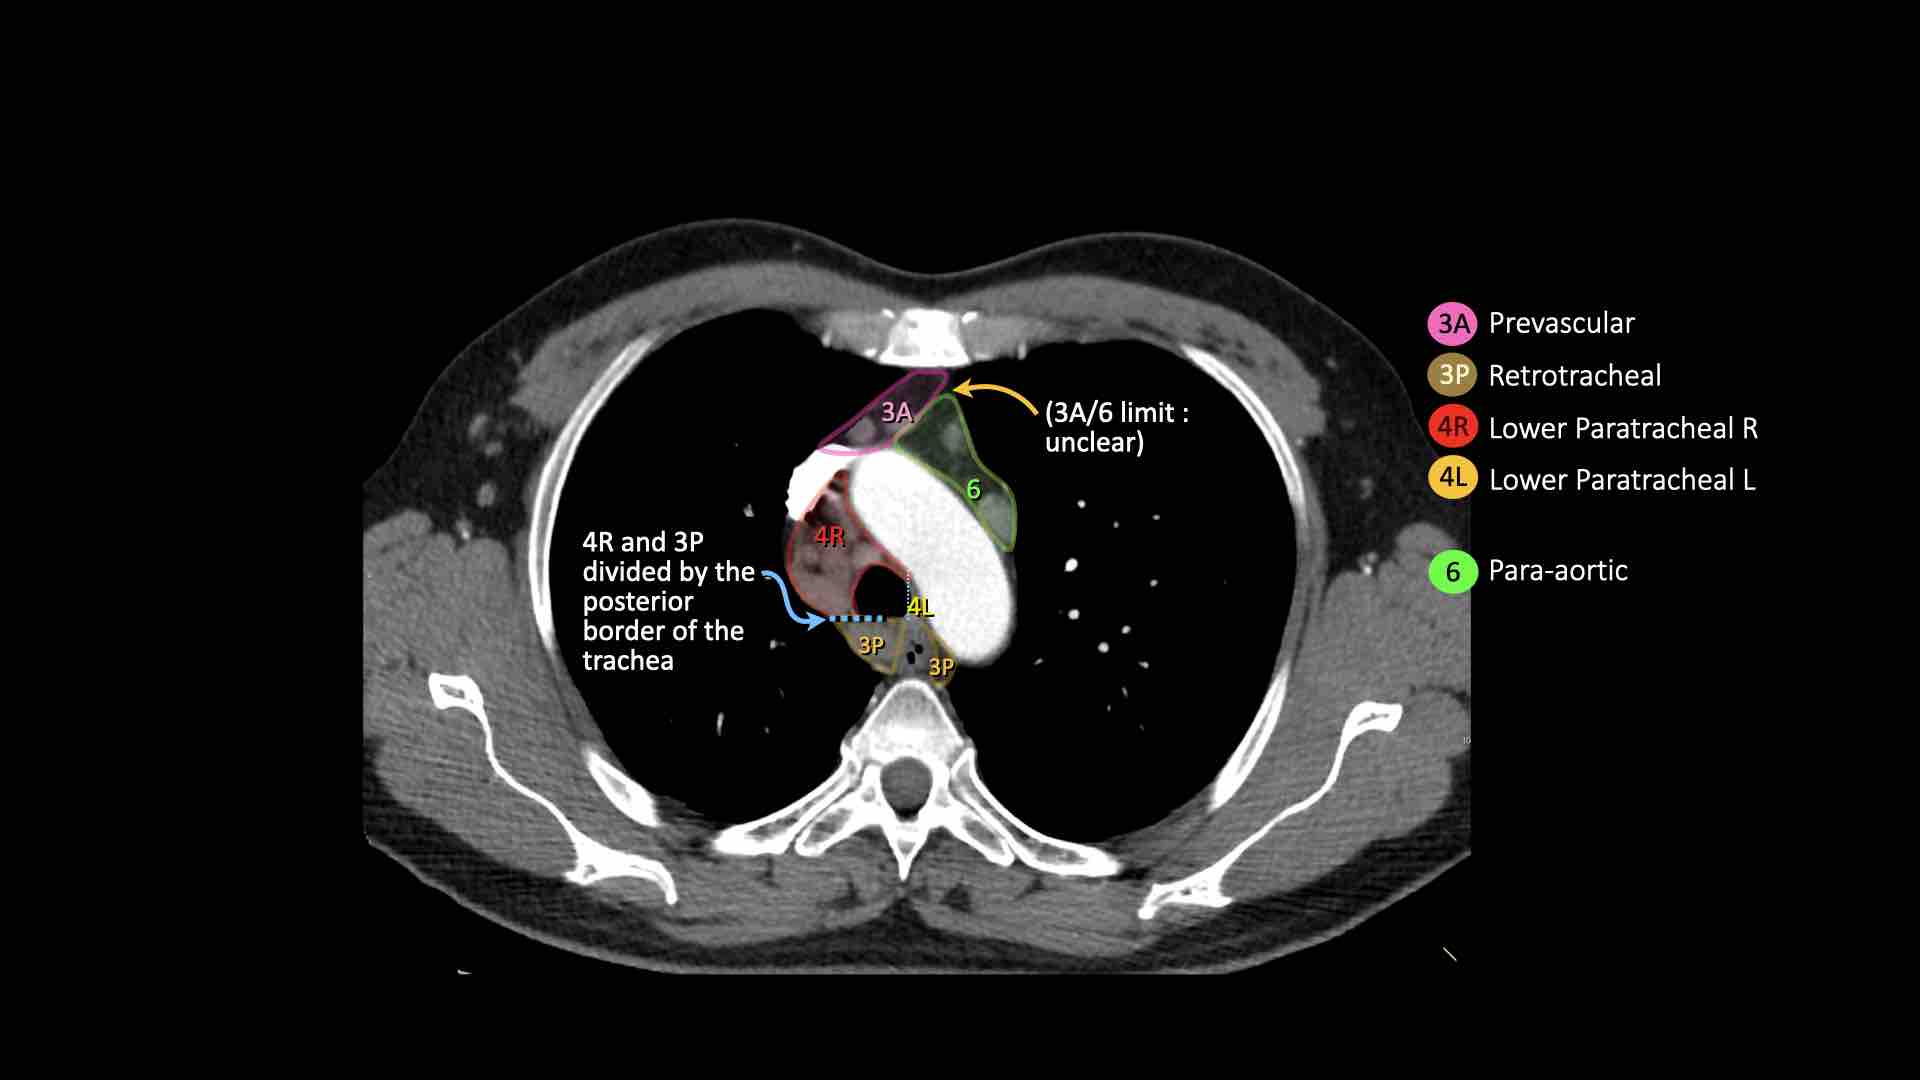

3A.Trước mạch máu

Các hạch này không tiếp giáp với khí quản như các hạch ở nhóm 2, mà nằm ở phía trước các mạch máu.

3P.Trước cột sống

Các hạch không tiếp giáp với khí quản như các hạch ở nhóm 2, mà nằm sau thực quản, tức là ở vị trí trước cột sống.

4R.Cạnh khí quản dưới

Từ điểm giao nhau giữa bờ dưới tĩnh mạch vô danh (tĩnh mạch tay đầu trái) với khí quản đến bờ dưới tĩnh mạch đơn.

Hạch nhóm 4R trải dài từ bờ bên phải đến bờ bên trái của khí quản.

4L.Cạnh khí quản dưới

Từ bờ trên của quai động mạch chủ đến bờ trên của động mạch phổi trái.

6. Cạnh động mạch chủ

Đây là các hạch của động mạch chủ lên hoặc hạch cơ hoành, nằm ở phía trước và bên của động mạch chủ lên và quai động mạch chủ.

Bên trái là hạch 3A nằm trong khoang trước mạch máu.

Lưu ý cũng có các hạch cạnh khí quản dưới bên phải, tức là hạch nhóm 4R.

Bên trái là hạch cạnh khí quản 4R.

Ngoài ra còn có một hạch động mạch chủ nằm bên ngoài quai động mạch chủ, tức là hạch nhóm 6.

Bên trái là hình ảnh ngay trên mức thân động mạch phổi, cho thấy các hạch cạnh khí quản dưới bên trái và bên phải.

Ngoài ra còn có các hạch nhóm 3 và nhóm 5.

Bên trái là hình ảnh ở mức phần dưới khí quản, ngay trên carina.

Bên trái khí quản là các hạch 4L.

Lưu ý rằng các hạch 4L này nằm giữa thân động mạch phổi và động mạch chủ, nhưng không nằm trong cửa sổ phế động mạch, vì chúng nằm ở phía trong dây chằng động mạch.

Hạch nằm bên ngoài thân động mạch phổi là hạch nhóm 5.